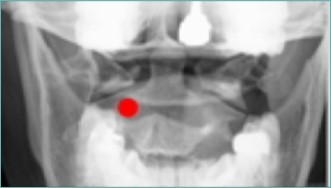

Figure 7.Anterior-posterior fluoroscopic view showing target site for Stealth needleÔ placement, medial to the superior pars of C2. (Image courtesy of Andrea Trescot, MD)

Anterior-posterior fluoroscopic view showing target site for Stealth needleÔ placement, medial to the superior pars of C2. (Image courtesy of Andrea Trescot, MD)